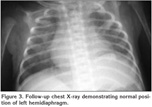

On the 26th day chest tube was replaced depending on the attempts to wean the patient from the ventilator were unsuccessful. He appeared distressed and hypoxic even on continuous positive airway pressure. On physical examination breath sounds were absent over the lower half of the left chest. Chest X-ray showed elevation of the left hemidiaphragm and ultrasonography of the diaphragm demonstrated absent movement during spontaneous breathing (Figure 2). The infant underwent to thoracotomy and plication of the left hemidiaphragm. He was successfully extubated on the second postoperative day. After three days of nasal continuous positive airways pressure, he subsequently required only 25% of supplementary oxygen. A chest X-ray 3 weeks later showed reexpansion of the left lung with normal diaphragmatic position (Figure 3). He was eventually discharged to home at 38 days of age.

Figure 2